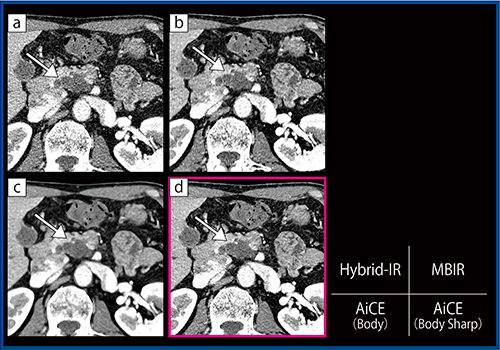

さらに,肝動脈末梢の描出についてHCC治療後症例(90歳代,女性:図4)の画像を比較したところ,AiCE(Body Sharp)(d)ではMBIR(b)と比べて遜色のない画像を得られた。ノイズについても,MBIRで見られる低周波ノイズはAiCE(Body Sharp)では目立たない。

図4 HCC治療後症例(90歳代,女性)の動脈相における肝動脈末梢の描出